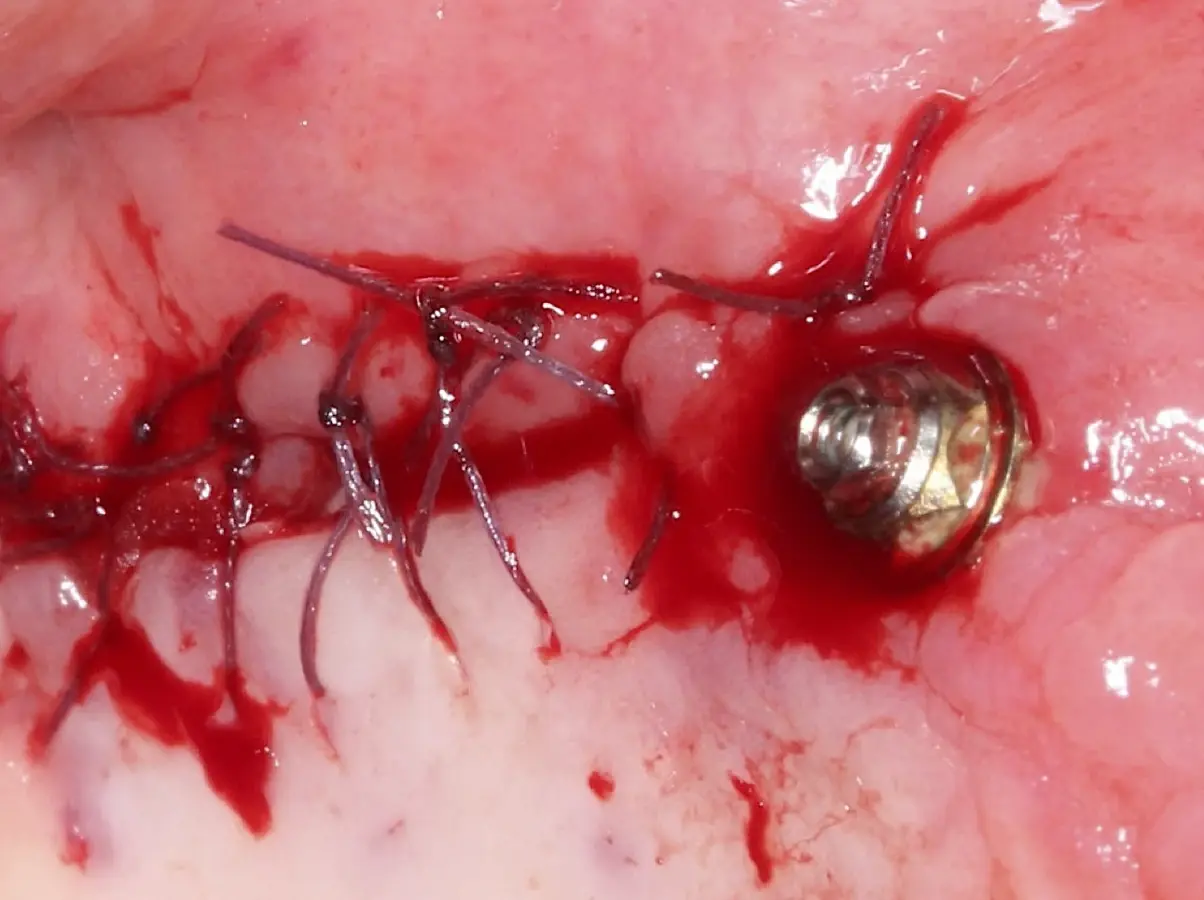

Finalizado el lado izquierdo, continuamos con el levantamiento de piso de seno maxilar del lado derecho.

Figura 22. Afrontamiento de colgajo y sutura.

Figura 23. Delimitación y osteotomía por desgaste de la ventana lateral con el inserto redondo de punta diamantada.

Figura 24. Fractura del bloque óseo con la ayuda de un martillo e instrumento romo.

Figura 25. Introducción del bloque óseo de la pared lateral dentro del seno maxilar: inicio del desprendimiento de la membrana con el inserto de presión hidráulica.